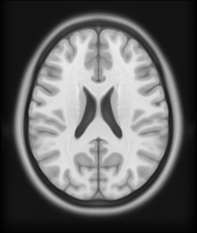

Figure 8: Example BRATS image with its decomposition result in atlas space. (a) Input image after pre-processing; (b) quasi-normal image L+M𝐿𝑀L+M; (c) non-brain image S𝑆S; (d) pathology image T𝑇T.

In addition to extracting the brain from pathological datasets, our method also allows for the estimation of a corresponding quasi-normal image in atlas space, although this is not the main goal of this paper. Fig.8 shows an example of the reconstructed quasi-normal image (L𝐿L) for an image of the BRATS dataset, as well as an estimation of the pathology (pathology image T𝑇T and non-brain image S𝑆S). Compared to the original image, the pathology shown in the quasi-normal image has been greatly reduced. Hence this image can be used for the registration with a normal image or a normal atlas. This has been shown to improve registration accuracy for the registration of pathological images [27]. Furthermore, an estimate of the pathology (here a tumor) is also obtained which may be useful for further analysis. Note that in this example image the total variation term captures more than just the tumor. This may be due to inconsistencies in the image appearance between the normal images (obtained from OASIS data) and the test dataset. As our goal is atlas alignment rather than quasi-normal image reconstruction or pathology segmentation, such a decomposition is acceptable, although we could improve this by tuning the parameters or applying regularization steps as in [27].